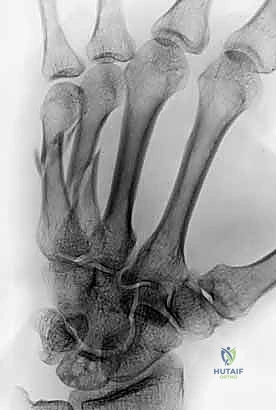

- الأشعة السينية (X-rays): يتم أخذ صور من زوايا متعددة (أمامية خلفية، جانبية، ومائلة) لتحديد موقع الكسر، نوعه (عرضي، حلزوني، مائل، متفتت)، ودرجة التزوي (Angulation).

خطوات التثبيت الجراحي - توثيق بصري (Intraoperative Imaging)

يحرص الدكتور هطيف على توثيق خطوات العمل الجراحي لضمان أعلى مستويات الدقة. نستعرض هنا مجموعة من الصور من داخل غرفة العمليات توضح مدى تعقيد ودقة هذه الجراحات:

معرض الصور الشعاعية: تقييم النتائج الجراحية (Post-Op X-rays)

النجاح الحقيقي يُقاس بالاستعادة المثالية للشكل التشريحي للعظم. توضح هذه الصور الشعاعية بعد الجراحة الدقة المتناهية في إعادة محاذاة العظام وتثبيتها.

التثبيت المحكم يسمح بالشفاء العظمي الأولي (Primary Bone Healing) دون تكوين كتلة عظمية كبيرة (Callus) قد تعيق حركة الأوتار المنزلقة فوقها.